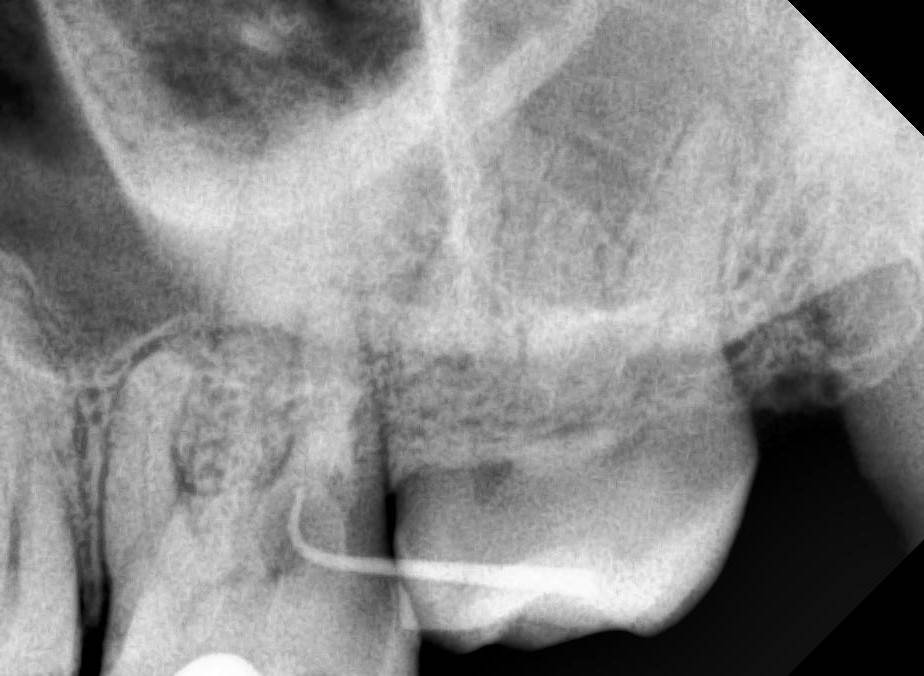

Kolchanov Опубликовано 19 августа, 2023 Поделиться Опубликовано 19 августа, 2023 Есть вот такой зуб 26. На дистальном корне рецессия, парадонтальный карман и дефект на корне явно не кариозного происхождения. Может кто покрутить КТ и сказать свои мысли по поводу процесса. https://drive.google.com/drive/folders/1B2huzkpPolt4XsAAIdYJuWwHHcJvr7iK?usp=drive_link Меня смущает, что, похоже, и на 28 (27 удалён) есть изменения и костная ткань тоже выглядит как-то подозрительно. Ссылка на комментарий

Kolchanov Опубликовано 22 августа, 2023 Автор Поделиться Опубликовано 22 августа, 2023 Симптоматики как таковой нет. Холодовая секунд пять. При перкуссии не боль, но неприятно. По анамнезу, говорит, что болел когда-то. Ссылка на комментарий

Carioznik Опубликовано 22 августа, 2023 Поделиться Опубликовано 22 августа, 2023 Кажется, как будто, пациент что-то там в этой область делал нехорошее, может вредная привычка какая? Ортодонтия там раньше была? Старые КТ-шки есть? Ссылка на комментарий